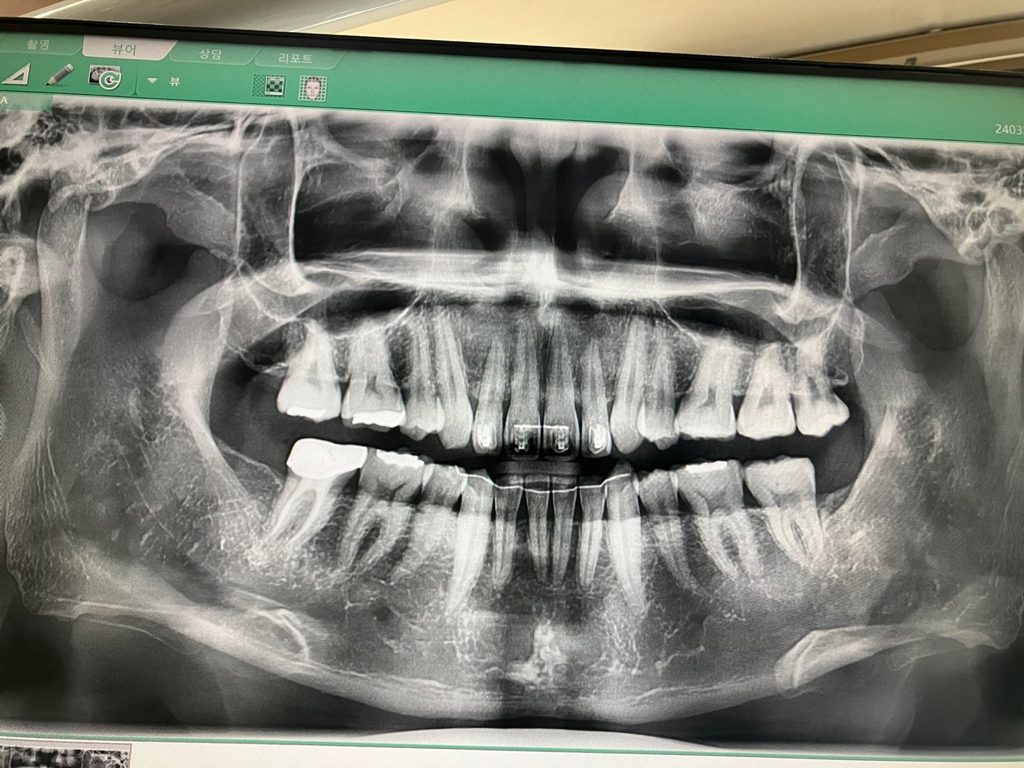

위 사진만 보고는 교합관계나 상악, 하악의 위치 관계를 정확히 파악하기는 어렵습니다. 현재 파노라마 방사선 사진상에서는 이전에 상,하악 발치교정을 시행했고 왼쪽 어금니 교합이 살짝 틀어져 있다는 것 정도만 알 수 있습니다.

파노라마 방사선 사진을 통해서는 교합 양상을 제대로 알 수 없으며, 아마 주치의선생님께서 육안으로 보시기에 그러한 판단을 내리신 것으로 보입니다.

파노라마 사진에서는 관찰할 수 없고 직접 눈으로 봐서 교합상태를 확인해야 알 수 있습니다.

파노라마 사진으로는 하악과 상악의 관계를 알수가 없습니다. 육안상으로 그렇다는게 아닐까 생각됩니다.

파노라마 사진으로는 화학이 뒤로 후퇴했는지 알 수 있는 방법이 없습니다. 화학이 뒤로 후퇴했는지를 확인해보기 위해서 일단은 세펄로라는 사진을 찍어보는 것이 좋습니다